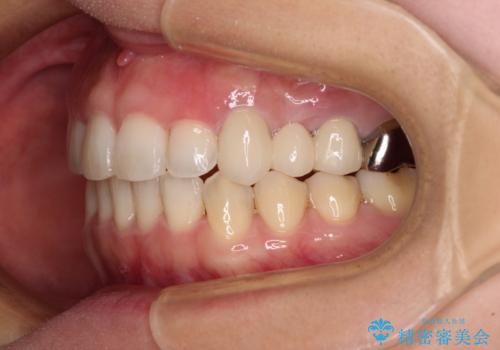

矯正治療後には切断したブリッジをオールセラミックブリッジに置き換えることとしました。

矯正治療中に上下前歯が接触しない時期があり、咬み合わせ改善のために期間がかかるのではないかと懸念されましたが、結果的には補綴治療も含めて1年以内の短期間で終えることができました。